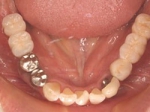

術後(鏡像)